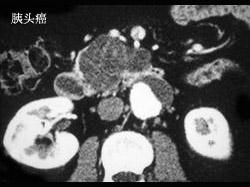

胆总管结石与胰头癌的主要鉴别特点是 ( )A、有无皮肤瘙痒B、有无肝功能改变C、有无淀粉酶改变D、有无肿大胆囊E、有无进行性黄疸

问题 胆总管结石与胰头癌的主要鉴别特点是 ( )

选项 A、有无皮肤瘙痒 B、有无肝功能改变 C、有无淀粉酶改变 D、有无肿大胆囊 E、有无进行性黄疸

答案 E